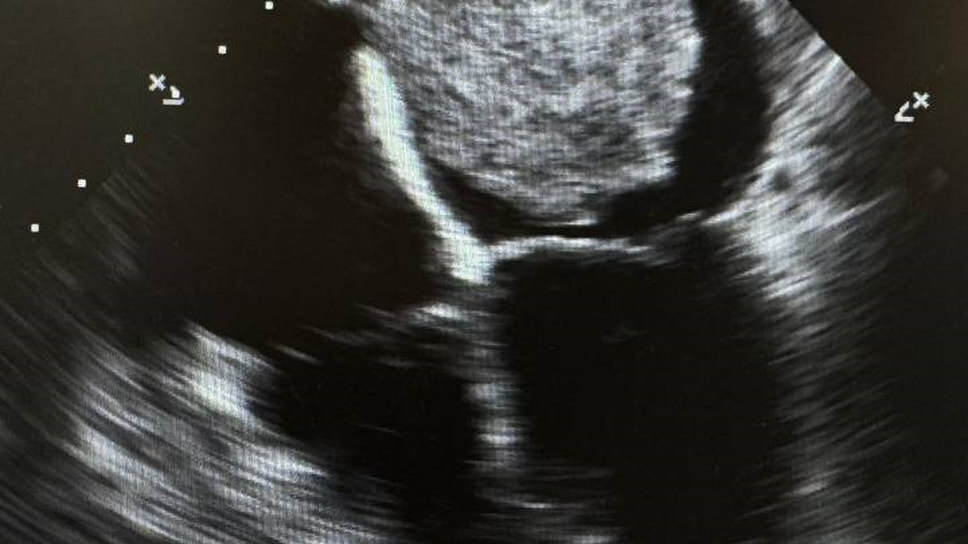

Кардиохирурги ДЦК и ССХ спасли 55-летнюю пациентку от огромной опухоли сердца, сообщили в медучреждении. Два года ее мучила одышка, но стандартные обследования не выявили причину. В сентябре состояние резко ухудшилось: одышка возникала даже при легких нагрузках. УЗИ сердца показало миксому размером 6,5x4,6 см, плюс недостаточность митрального и трикуспидального клапанов 2-3 степени.